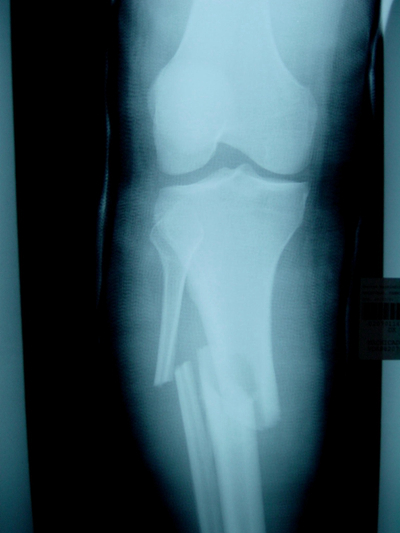

骨折圖片